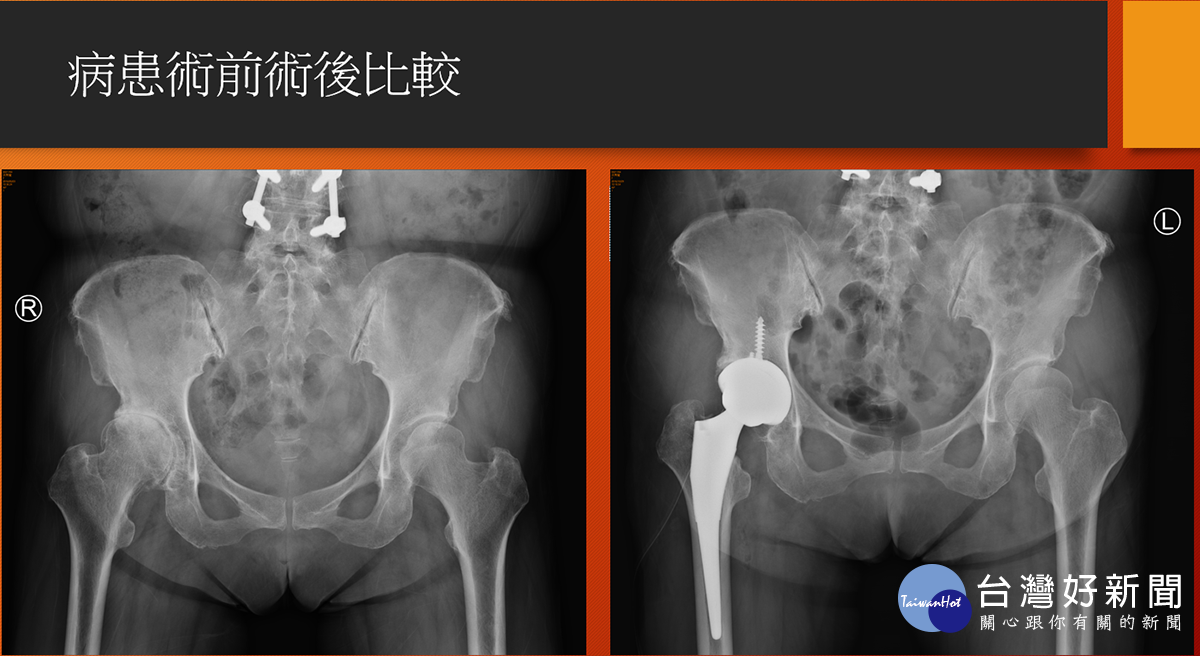

病人術前術後X光比較。(圖/七賢脊椎外科醫院提供)

高雄市一名63歲謝姓婦女在20多年前一場車禍, 造成右腳無法出力,中間歷經中醫針灸、骨傷、復健治療, 但因美髮師工作得長期站立,依靠左腳出力支撐, 卻又讓左腳開始產生疼痛, 直至去年底才在骨科門診中發現雙邊髖關節都已磨損嚴重, 醫師建議以“正前開”髖部手術,先處理持續疼痛感的左邊髖關節, 術後謝女士表示幾乎沒有疼痛感, 並在今年又另安排右邊髖關節置換手術, 順利解決謝女士多年的髖部疼痛不適。

七賢脊椎外科醫院骨關節科副院長楊華偉醫師說明, 一般在面臨人工髖節置換手術後的病人常遇到有疼痛、長短腳、 脫臼、復原時間較長等問題,但若是以正前開手術都可克服, 只是醫師在手術困難度上相對提高, 過去在國外文獻上統計之病人術後效果也非常良好, 目前在本院之案例也已達50人, 追蹤病人對於術後反應均以正面回饋。

楊華偉強調,正前開陶瓷人工髖關節手術, 其中陶瓷可解決磨損與腐蝕問題,也大幅降低二次開刀機會, 另外正前開之先進手術更能進一步改善常見術後之疼痛與復原時間問 題。而正前開手術對於嚴重骨鬆與體重過重BMI大於40的病人較 不適合,目前針對正前開之手術費用是健保給付範圍內, 除置換之髖關節自費材料外,不需有其他額外手術費用負擔。 有任何髖關節治療問題定要找專業骨科醫師做諮詢, 以選擇最適合個人的治療方式。